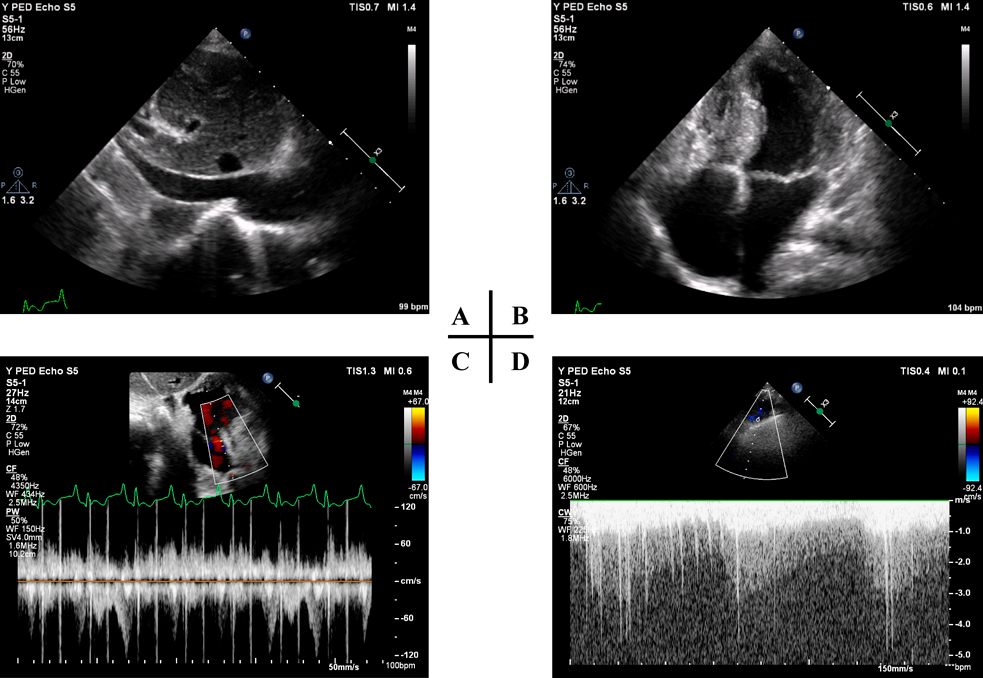

心臓カテーテル検査前日の血液検査(Table 1)で,BUN 40 mg/dL, SCr 0.79 mg/dL, SCrから推定した糸球体濾過量(eGFRcreat) 69.9 mL/min/1.73 m2と,軽度の腎機能低下を認めた.随時尿で150 mg/gCrの微量アルブミン尿を認め,潜血は陰性だった.同日の胸部X線(Fig. 1A)では,心胸郭比63.3%と定期外来受診時と同程度の心拡大および肺うっ血所見であった.入院22日目の心エコー検査では,下大静脈径14.9 mmと拡大し,呼吸性変動は乏しかった(Fig. 2A).両心房の拡大を認め(Fig. 2B),心房間交通は8.9 mmと狭小で右左短絡であった(Fig. 2C).右BTシャント血流は明瞭に描出できたが(Fig. 2D),左BTシャント血流は描出できなかった.

Pediatric Cardiology and Cardiac Surgery 36(2): 166-172 (2020)

Fig. 2 Two-dimensional transthoracic echocardiography showing dilated inferior vena cava (A), interatrial right-to-left shunt of atrial septal defect using pulsed mode (B), dilated both atria (C), Blalock–Taussig shunt flow using continuous mode (D)